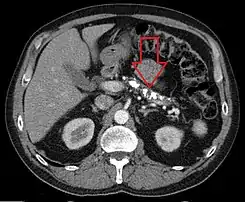

TC axial que muestra múltiples calcificaciones en el páncreas en un paciente con pancreatitis crónica

El diagnóstico de la pancreatitis crónica es difícil. Los análisis de sangre habitualmente no son útiles. Las pruebas diagnósticas más importantes son las de imagen.[6] [7] La presencia de calcificaciones pancreáticas en una radiografía simple de abdomen es diagnóstico de pancreatitis crónica pero lo más frecuente es que no se vean. Existen muchas otras pruebas de imagen que nos permiten llegar al diagnóstico: ecografía, tomografía axial computarizada y resonancia magnética del abdomen, endoscopia digestiva con inyección de contraste en el páncreas (colangiopancreatografía retrógrada endoscópica o CPRE) o ecografía a través de endoscopia digestiva (ecoendoscopia). Existen otras pruebas que sirven para medir la capacidad de funcionamiento del páncreas.